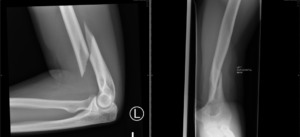

Case 2 - Arm Injury

A 30 year old lady, presents to ED with an injury sustained while weight lifting at the local gym.

1) Describe the X-ray